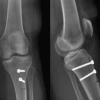

A 6-year-old girl presented to our unit following a fall at school onto an outstretched hand. She was known to our unit having had sustained a mid-shaft both bone forearm fracture (Fig. 1a) which was subsequently treated with flexible IM titanium elastics nailing system (TENS) (IM, intramedullary; TENS DePuy Synthes) nails 5 months prior (Fig. 1b).

ESIN nails are composed of titanium (Ti-6Al-4V), with a modulus of elasticity closer to the bone than stainless steel. On presentation to ED, she had an obvious right upper limb deformity (Fig. 2) but denied pain. This was an isolated injury, she was clinically stable and her distal neurovascular status was intact. X-rays revealed a fracture through her previous fracture site (Fig. 3a). She was brought to theater and managed through a closed reduction under general anesthesia, correcting the angle of the IM nails until acceptable reduction was achieved (Fig. 3b). Our patient was discharged well the following day. She went onto have an excellent recovery, routine follow-up in clinic allowing for confirmation of radiological and clinical fracture union (Fig. 4a). The IM nails were then removed 6 months following her refracture (11 months total in situ, Fig. 4b) and she has been since discharged well from our service.